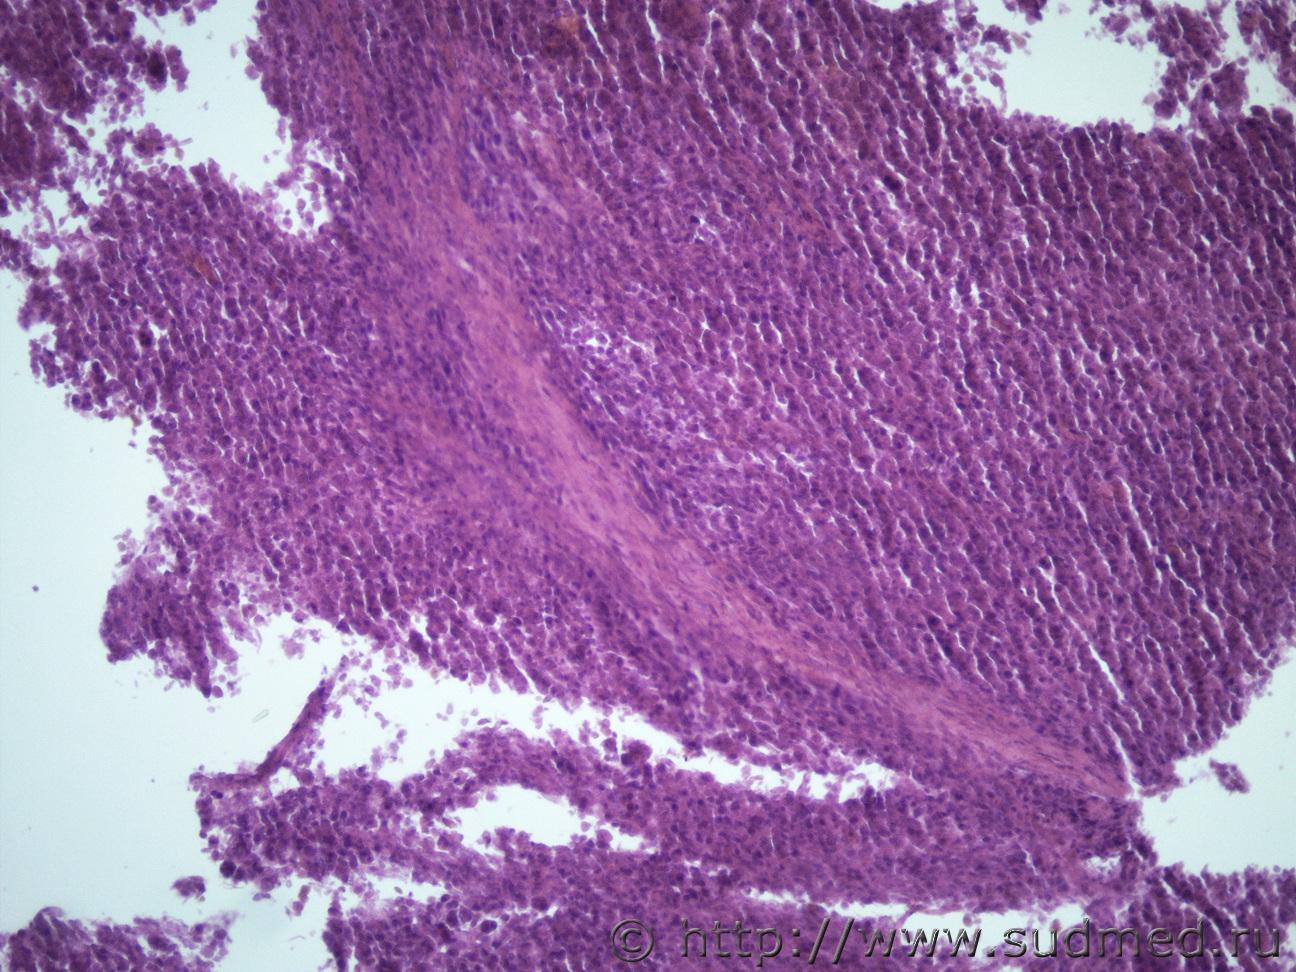

Ув. коллеги, представляю вашему вниманию опухоль в мягких тканях грудной клетки, сердце и почке. Муж 60 лет. Макро картины не знаю, эксперт не посчитал нужным это сообщать. Мягкие ткани Судебная медицина - Прикрепленное изображение Судебная медицина - Прикрепленное изображениеСудебная медицина - Прикрепленное изображениеСудебная медицина - Прикрепленное изображение Почка Судебная медицина - Прикрепленное изображение Судебная медицина - Прикрепленное изображениеСудебная медицина - Прикрепленное изображение Сердце Судебная медицина - Прикрепленное изображение Судебная медицина - Прикрепленное изображениеСудебная медицина - Прикрепленное изображениеСудебная медицина - Прикрепленное изображение

Саркома? Ван-Гизон...

Может остановиться на фибросаркоме ?

Тоже об этом подумала)))